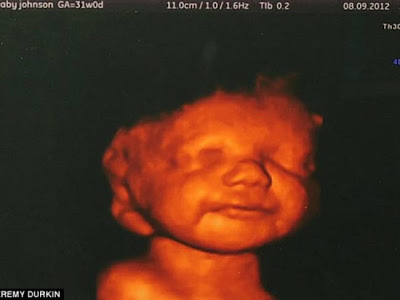

Η συμβουλή των γιατρών ήταν να κάνει έκτρωση όμως ένα χαμόγελο της άλλαξε γνώμη. Ήταν το χαμόγελο του αγέννητου μωρού της στο τρισδιάστατο υπερηχογράφημα. Mπόρεσε να δει πεντακάθαρα το μωρό της να χαμογελά, να κλωτσά και να κουνά τα χεράκια του, με αποτέλεσμα να συγκινηθεί τόσο ώστε να μην μπορέσει να προχωρήσει στην έκτρωση όπως αναφέρει η Daily Mail.